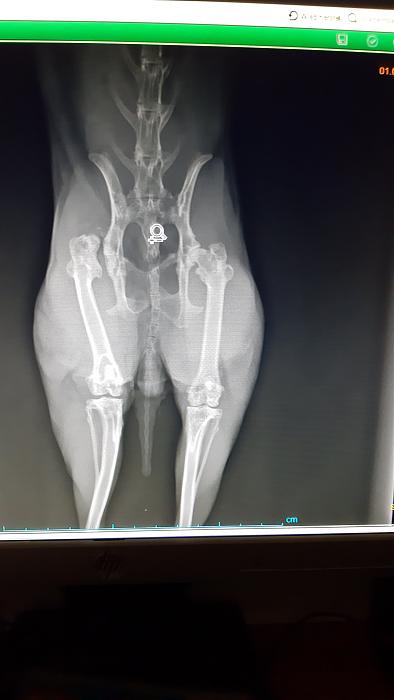

Hey, hier ist Ida. Bäh, meine Woche war gar nicht toll. Mama hat gemerkt, dass ich durchhänge. Ich habe mein kaputtes Bein stark entlastet und mich auch sonst mehr zurückgezogen. Ab Do hat mir Mama dann Metacam gegeben. Bei der Medi-Gabe, die ich wirklich extrem hasse, hat sie am anderen Fuß ein kleines Sohlengeschwür entdeckt. Das hat sie dann darin bestätigt, dass ich shcon ne Weile wohl Probleme hatte und mein Bein entlaste.

Gestern wurde ich dann zum Tierarzt geschleppt. Röntgen. Meine Hüfte hat sich nicht verändert, der Hüftkopf fehlt ja von Geburt an und hat sich auch nicht zugebildet. Aber leider ist meine Knochendichte nicht in Ordnung.